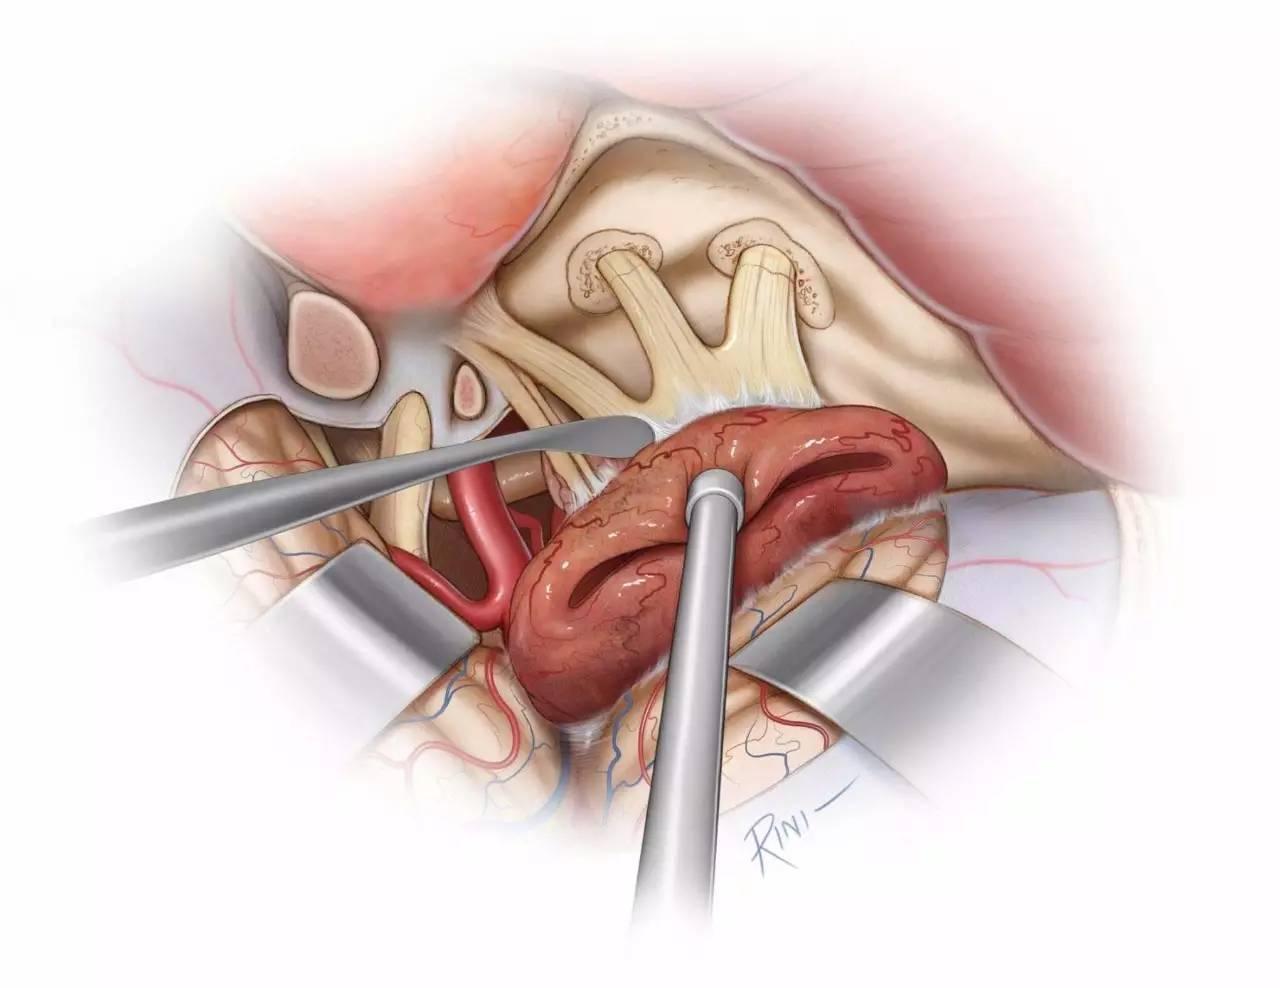

图11:将肿瘤从半月神经节上仔细分离。在保证安全的前提下,切除侵入三叉神经各骨孔内的肿瘤,必要时可扩大这些骨孔。

图12:切除肿瘤后最终的术野。滑车神经周围残留少量肿瘤,以避免永久性神经功能障碍。